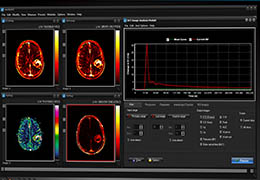

ANYTHINK 经导管主动脉瓣膜置换术分析系统